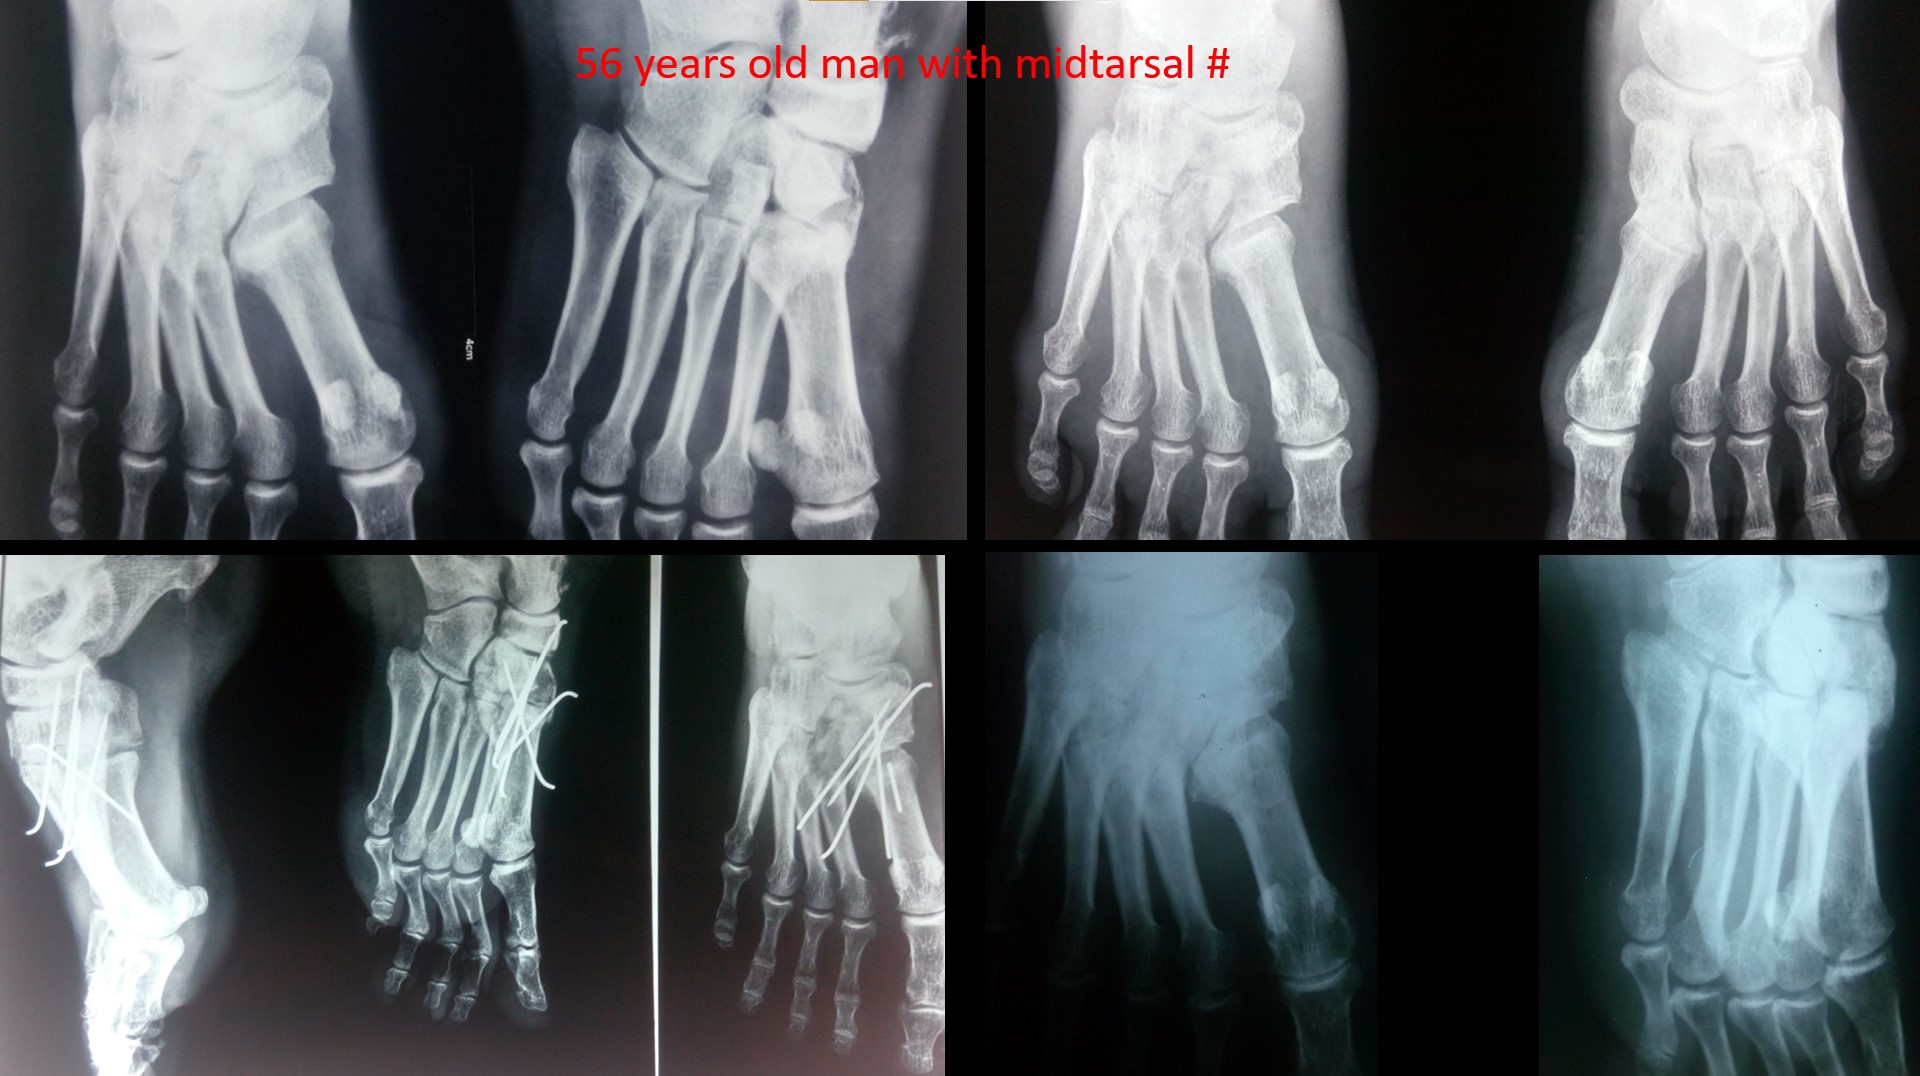

MIDTARSAL INJURY